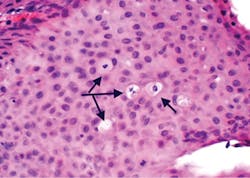

Figure 2: Histology of multifocal epithelial hyperplasia with arrows pointing to the mitotic figures (mitosoid cells) commonly found in this type of lesion. Koilocytosis associated with HPV is also found in MEH.

Figures 1–3 depict multifocal epithelial hyperplasia. The actual growth is usually 1 mm to 10 mm, but because the papules often coalesce, they may appear larger. The term multifocal is used because they most often occur at multiple sites as variable numbers of papules (as seen in figure 1) along the lateral border of the tongue. The papules are circumscribed, soft, and flat.